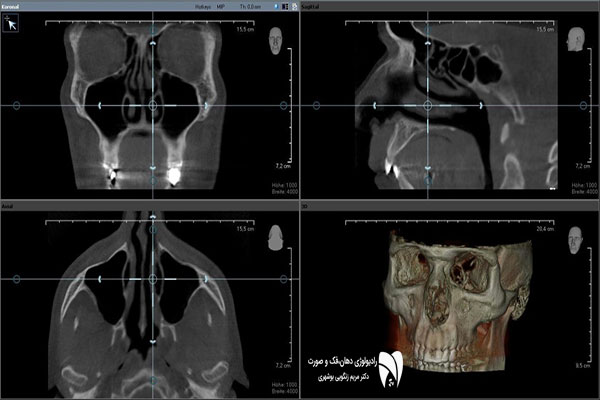

فتوگرافی ارتودنسی شامل عکس هایی از زاویه های مختلف چهره و دندانهاست که باید بسیار دقیق و با کیفیت واز زاویای استاندارد تهیه شود . فتوگرافی ارتودنسی اسکن دقیقی از وضعیت و پارامترهای چهره ، طرح لبخند و دندان های شما به دندانپزشک می دهد و به او کمک می کند تا برای شما بهترین طرح درمان متناسب با پارامترهای صورت طراحی کند و همین طور فرایند پیشرفت درمان را کنترل نماید. با توجه به اهمیت فتوگرافی دندان، بیماران باید در انتخاب بهترین رادیولوژی دهان، فک و صورت دقت بیشتری داشته باشند.

گاهی اوقات در معاینه اولیه دندانپرشک متوجه نقایص و مشکلات بیمار خود نمی شود . فتوگرافی دندان پزشکی و ارتودنسی کمک می کند تا دندانپزشک به دید کلی از وضعیت دندان های شما دست یابد و طرح درمان مناسب ارتودنسی ، ونیرکامپوزیت ، لمینت دندان یا ایمپلنت تجویز کند .عکس پزشکی باید به گونه ای استاندارد انجام شده باشد که پزشک بتواند با استناد به آن طرح درمان دقیقی را طرح ریزی کند .